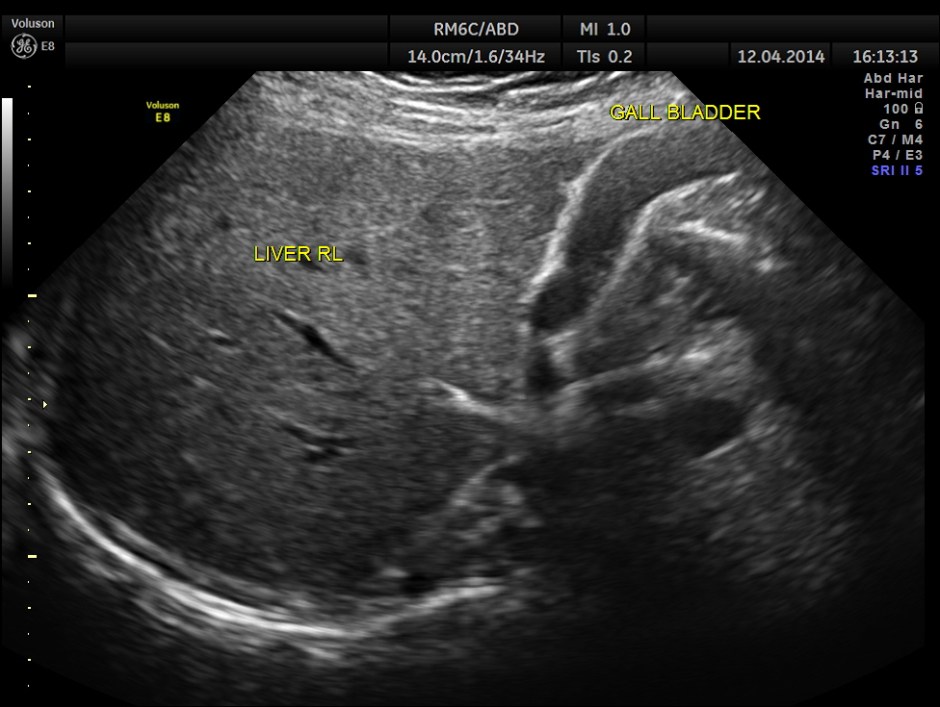

The following pictures show a normal liver, gall bladder, pancreas and spleen .